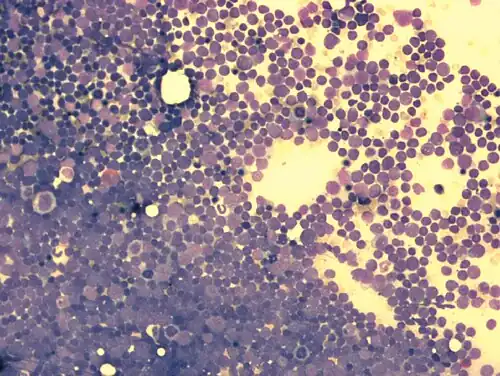

Zytomorphologie

Durch mikroskopische Untersuchung des Knochenmarks oder des Blutausstrichs bei leukämischem Verlauf kann die Diagnose einer akuten Leukämie gestellt werden. Für die weitere Subklassifikation der ALL spielt die Beurteilung der Zellmorphologie im Gegensatz zur AML nur eine untergeordnete Rolle. In der sogenannten FAB-Klassifikation („French-American-British“) wird zwischen drei verschiedenen Morphologien unterschieden (L1, L2, L3). Von Bedeutung ist das nur für den seltenen L3-Subtyp, der mit der „reifzelligen B-ALL“ assoziiert ist. Die reifzellige B-ALL ist eine Sonderform der ALL und kann als die leukämische Manifestation des Burkitt-Lymphoms betrachtet werden (d. h. ein Burkitt-Lymphom mit >20 % oder >25 % Knochenmarkbefall) und wird wie dieses behandelt. Die Unterscheidung zwischen L1 und L2-Morphologie ist dagegen schwierig und selbst sehr erfahrene Hämatologen oder Hämatopathologen kommen hier zu unterschiedlichen Einschätzungen. Klinisch hat die Unterscheidung von L1 und L2 keine Bedeutung.